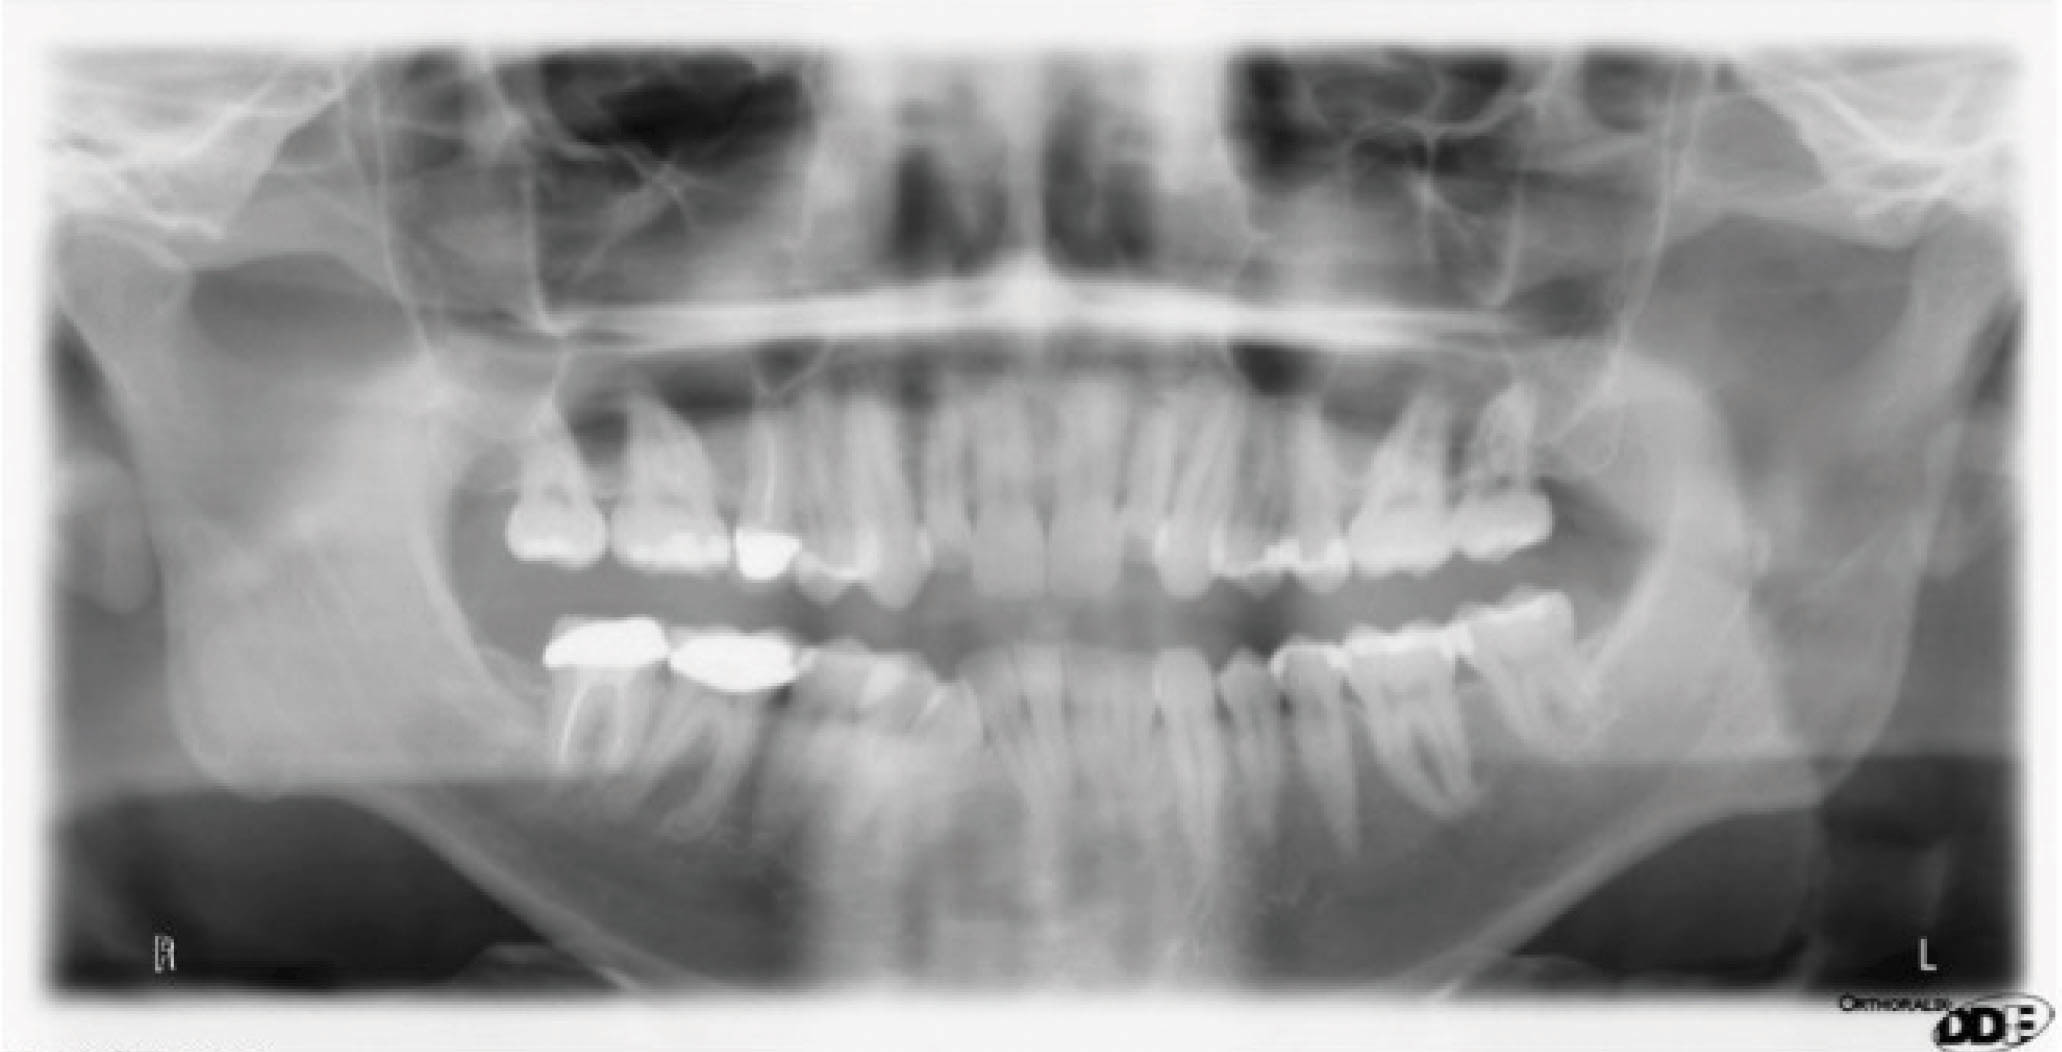

نتایج درمان (شکل 20-6) و عکس طراحی کامپیوتری (شکل 21-6) خیلی به هم شبیه شدند. عکس OPG هم طبیعی است.

شکلهای 26-6 و 27-6 نتایج درمان در قیاس با طراحی کامپیوتری را نشان میدهند. عکس OPG هم طبیعی است (شکل 28-6).

با سوپرایمپوز کردن لترال سفالومتری در شکل 35-6 شاهد سه درجه پروترود شدن انسیزورهای پایین هستیم. ارتفاع عمودی ثابت ماند و کنترل خوبی در حفظ زاویه پلن مندیبل داشتهایم. رادیوگرافی OPG پایان کار (شکل 36-6) طبیعی است. مدت نگهدارنده ۳۰ ماه بود و همه چیز خوب حفظ شده است (شکل 37-6).

بیمار بعدی یک بیمارکلاسI با میزان متوسطی از کرادینگ در هر دو فک است. به کانینهایی که شدیداً چرخیدهاند دقت کنید (شکل 15-6 تا 17-6). این بیماران به ارتودنسی شفاف عالی جواب میدهند. یک دختر دبیرستانی که نمیخواهد در جشن فارغ التحصیلی خود و عکسهایی که در کلاس میگیرد براکت داشته باشد، خیلی خوب از الاینرهای شفاف استفاده میکند.

شکل 15-6

شکل 16-6

شکل 17-6